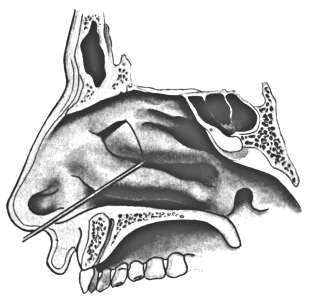

| 345. | Catheterizing the Sphenoidal Sinus | 654 |

| 320. | Catheterizing the Maxillary Sinus | 626 |

| 333. | Catheterizing the Frontal Sinus | 639 |